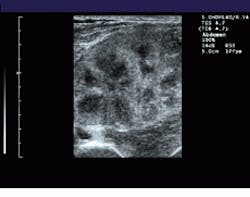

To increase the FOV in its Elegra system, Siemens combines the real-time imaging capability of modern ultrasound transducers with the ability to generate images over large fields of view. To do so, the system registers sequentially acquired image frames, estimates transducer motion, and constructs a panoramic view of the extended FOV in real time (see Fig. 1).

FIGURE 1. To extend the field of view (FOV) of ultrasound, the system registers sequentially acquired image frames and constructs a panoramic view of the extended FOV in real time. A comparision between a standard linear field of view of a renal transplant (bottom) and a wider, panoramic field of view (top) illustrates the effects of the process.